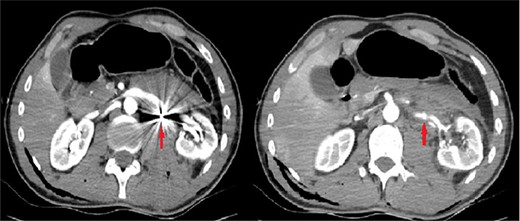

The patient was re-evaluated with CTA 3 weeks after discharge. Endovascular intervention was planned after observing that the left RAP was enlarged to 6 mm (Fig. 2). A renal angiogram was performed. After selectively catheterizing the left renal artery, a 6 × 3 mm filling extending inferiorly in the middle part of the left renal artery compatible with RAP was observed (Fig. 3). Following catheterization of the left renal artery with a long sheath, the lesion segment was passed with guide wire-catheter manipulations. Subsequently, a 6 × 22 mm covered stent (Advanta V12 Balloon Expandable Covered Stent, AMC, USA) was placed to include the RAP neck, and full expansion of the balloon and stent was achieved (Fig. 3). The control images revealed that the RAP was excluded from circulation, and the stent was patent. No embolism or bleeding was observed in the distal renal artery branches.

Tomographic angiography image of the enlarged renal pseudoaneurysm and the retained bullet core.